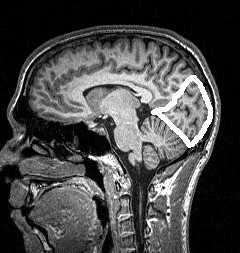

МРТ головного мозга. Границы лобной, теменной, височной и затылочной долей на сагиттальном срезе.

Для разграничения теменной доли надо ещё найти теменно-затылочную борозду (sulc. parietooccipitalis). Эта борозда в сагиттальной плоскости прослеживается на срединном и медиальных срезах. Она идёт от поверхности мозга вниз, имеет значительную протяжённость и нередко бывает сегментированной. В поперечной плоскости теменно-затылочная борозда отходит почти перпендикулярно межполушарной щели (рис.36) и даёт много мелких ветвей. Таким образом, границами теменной доли служат с лобной долей - центральная борозда, с затылочной - теменно-затылочная борозда, с височной - Сильвиева щель и верхняя височная борозда (угловая извилина).

МРТ головного мозга. Медиальный сагиттальный срез. Теменно-затылочная борозда (стрелка).

МРТ головного мозга. Границы теменной доли на медиальном сагиттальном срезе.